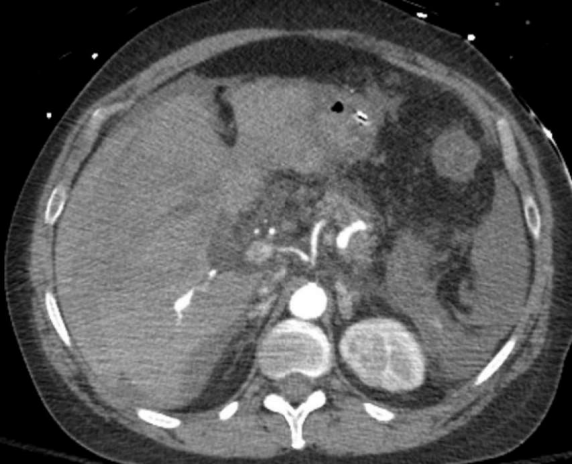

58 F 上腹部疼痛和低血压

疼痛是脾假性动脉瘤临床表现的典型症状,动脉期CT扫描对比显示脾动脉或其脾内分支对比并被血肿包围。对这一发现的最佳描述可能是血肿,它描述了所有假性动脉瘤的疾病和破裂风险。由于它们中的大多数在没有治疗的情况下涉及破裂的风险,因此所有的治疗都应该进行治疗,无论其大小或表现如何。